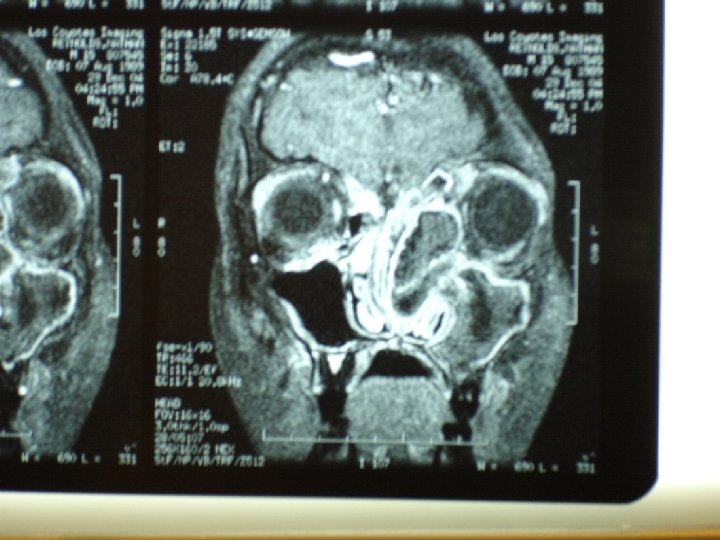

Chronic rhinosinusitis • Sinus CT scan • Consider anatomic factors— septal deviation, nasal polyps, concha bullosa, ostio-meatal blockage